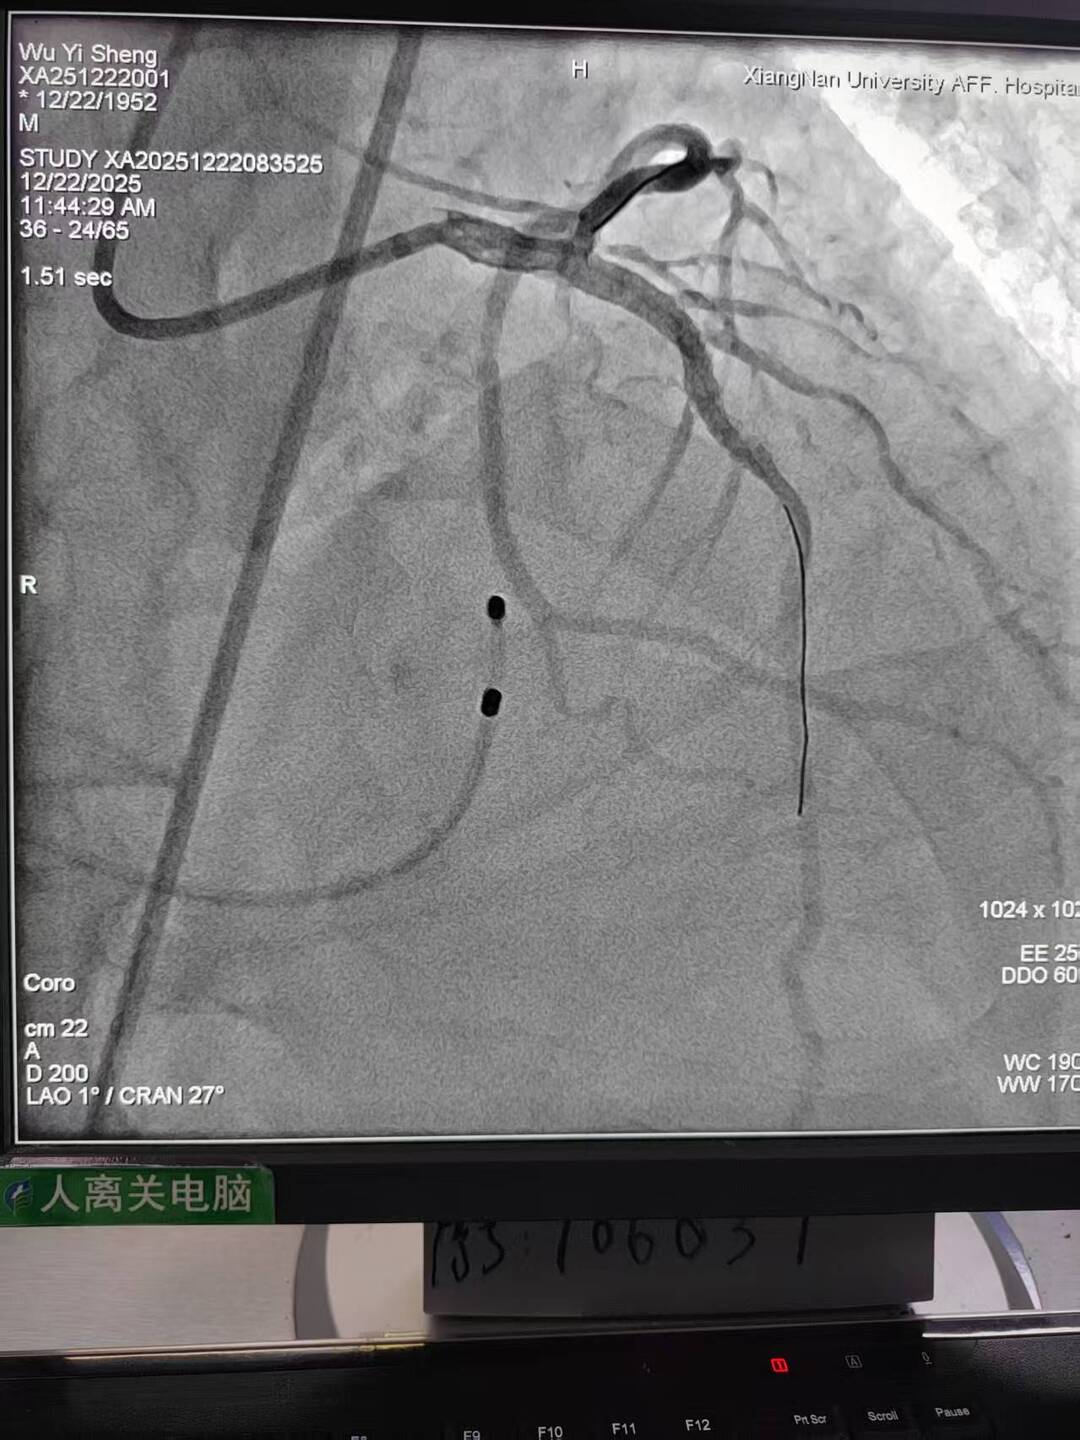

73岁的李先生因反复胸痛、气促入院,活动能力明显受限。经全面检查发现,其冠状动脉主干及多支血管存在多处严重狭窄,心肌供血严重不足;被称为“心脏大门”的主动脉瓣重度钙化、狭窄,已引发心功能衰竭;而外周血管同样存在严重钙化、溃疡与狭窄。这三种病变单独存在均足以危及生命,叠加后使传统外科开胸手术风险陡增,患者一度面临治疗困境。

手术过程犹如在心脏内进行的“微雕”和“换门”工程,步骤环环相扣,每一步都考验着术者的技术功底与团队协作默契。术中,团队首先利用先进的可扩张血管鞘,在严重钙化狭窄的右侧股动脉腔内成功建立安全的手术通路;随后经该微创入路,先通过球囊扩张术为冠状动脉植入支架,快速恢复心肌血供;紧接着,在同一手术台、同一入路下,精准将人工主动脉瓣输送至病变位置并成功释放,顺利替换失灵的原生瓣膜。整个过程中,团队成功克服了外周血管入路困难的核心挑战,确保手术各环节无缝衔接、精准落地。